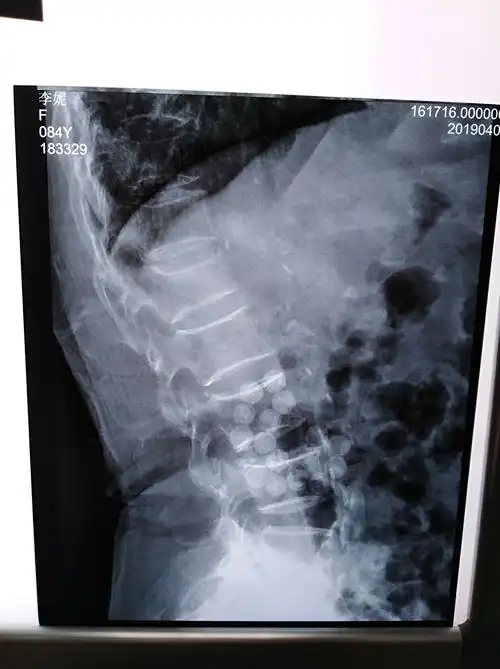

术前dr示腰1椎体压缩骨折